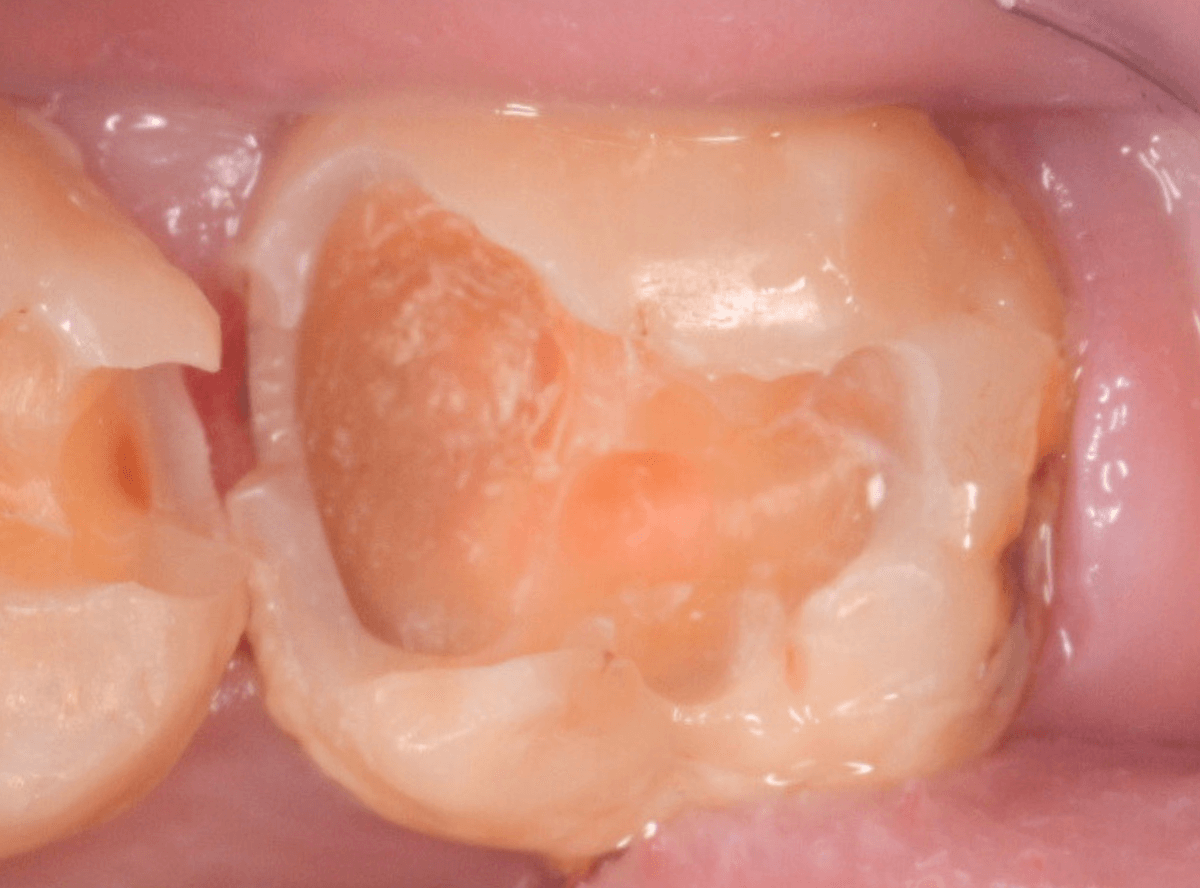

中のお薬も慎重に外して虫歯を除去します。

虫歯が深く、歯肉の下まで浸食していましたので、歯肉を部分切除し、虫歯を全て除去したところで、奇跡的に神経スレスレの状態でとどまっていました。

何とも言えませんが、神経を残せる可能性が出てきました。

虫歯が神経まで達していなくても、治療前から自発痛(何もしなくても痛い)があれば、神経をとらなければいけません。

今回は、そこまでの症状がありませんでしたので、患者さんと相談の上、神経を取らずに残す方法で様子を見る事になりました。

痛みが出ませんように。。。